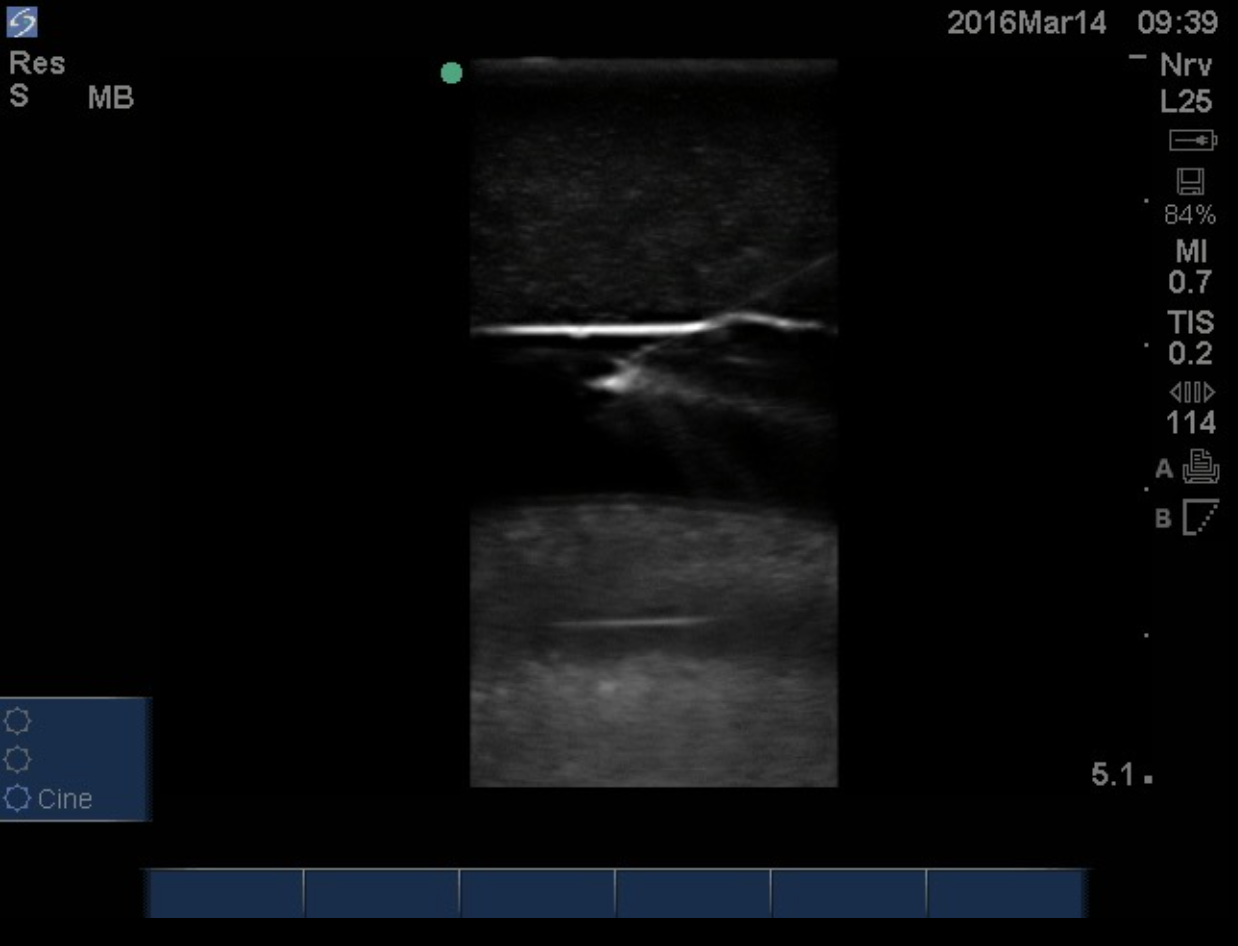

5.) Before prepping and draping the area, use the low frequency US transducer to identify the superior border of the effusion, the respiratory motion of the diaphragm, consolidated lung deep to the effusion and the liver or spleen caudally depending on the laterality of the procedure. Using a marking pen or the end of a needle cap, place a mark 1-2 intercostal spaces below the superior aspect of the fluid level in the mid-scapular or posterior axillary line just superior to the rib to avoid the neurovascular bundle that runs inferior to the rib. Do not mark below the 9th rib to avoid diaphragmatic or abdominal organ injury when the needle is inserted. For reference, the inferior tip of the scapula is at the 7th rib in the average, upright adult with the arms by the side. During this step, the depth of the superficial border of the pleural space and the center of the fluid collection should be measured to estimate the depth of needle insertion.

9.) Using the sterile high-frequency probe, verify the location of the fluid pocket deep to the skin wheel. The proceduralist may chose to measure the depth the needle will have to be inserted to reach the effusion at this step as well. (4)

10.) Next, with the transducer in the transverse orientation, introduce the needle alongside the transducer using the “in-plane” method and visualize the needle entering the pleural space while intermittently aspirating and injecting as the needle progresses through the subcutaneous tissues to adequately anesthetize the subcutaneous tissue. Inject the remaining anesthetic at the parietal pleura which is typically the most painful portion of the procedure.